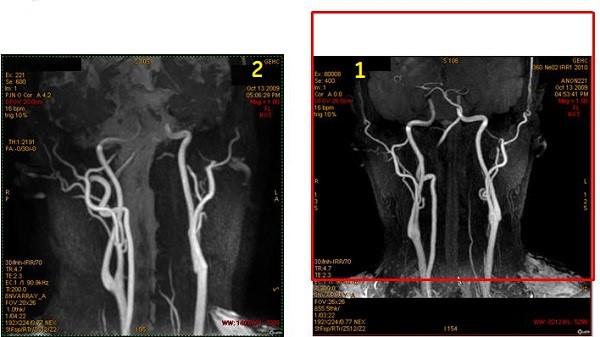

Figure 9. Coronal localizer with IR band and resultant coronal carotid image

Table 7. Image legend

NumberDescription

1Coronal localizer with superior axial IR band (red box) applied to saturate venous flow.

2Resultant Inhance Inflow IR coronal image of carotids.